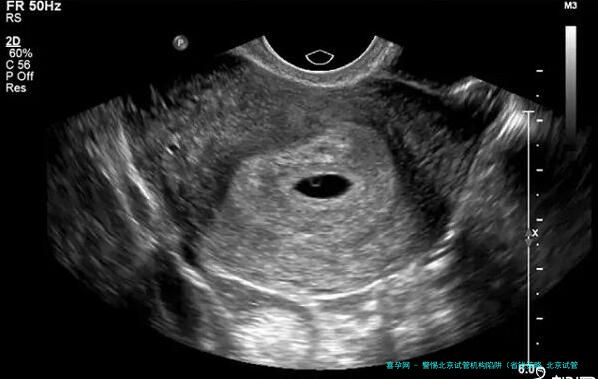

以北京某有名声辅助生殖中心作为例子,该机构享有国内有声誉的试管专业人士集体,多年来专注于试管婴儿技术的研究与临床实行,积聚了丰厚的经验。该机构的试管成功率稳固在百分之六十五左右,身在业界前沿水平。同一时刻,该机构在费用方向施行标明价格,整个试管周期的费用在八万元左右,无任何隐蔽性破费,让病人明精确白花费,安心里踏实心治疗。